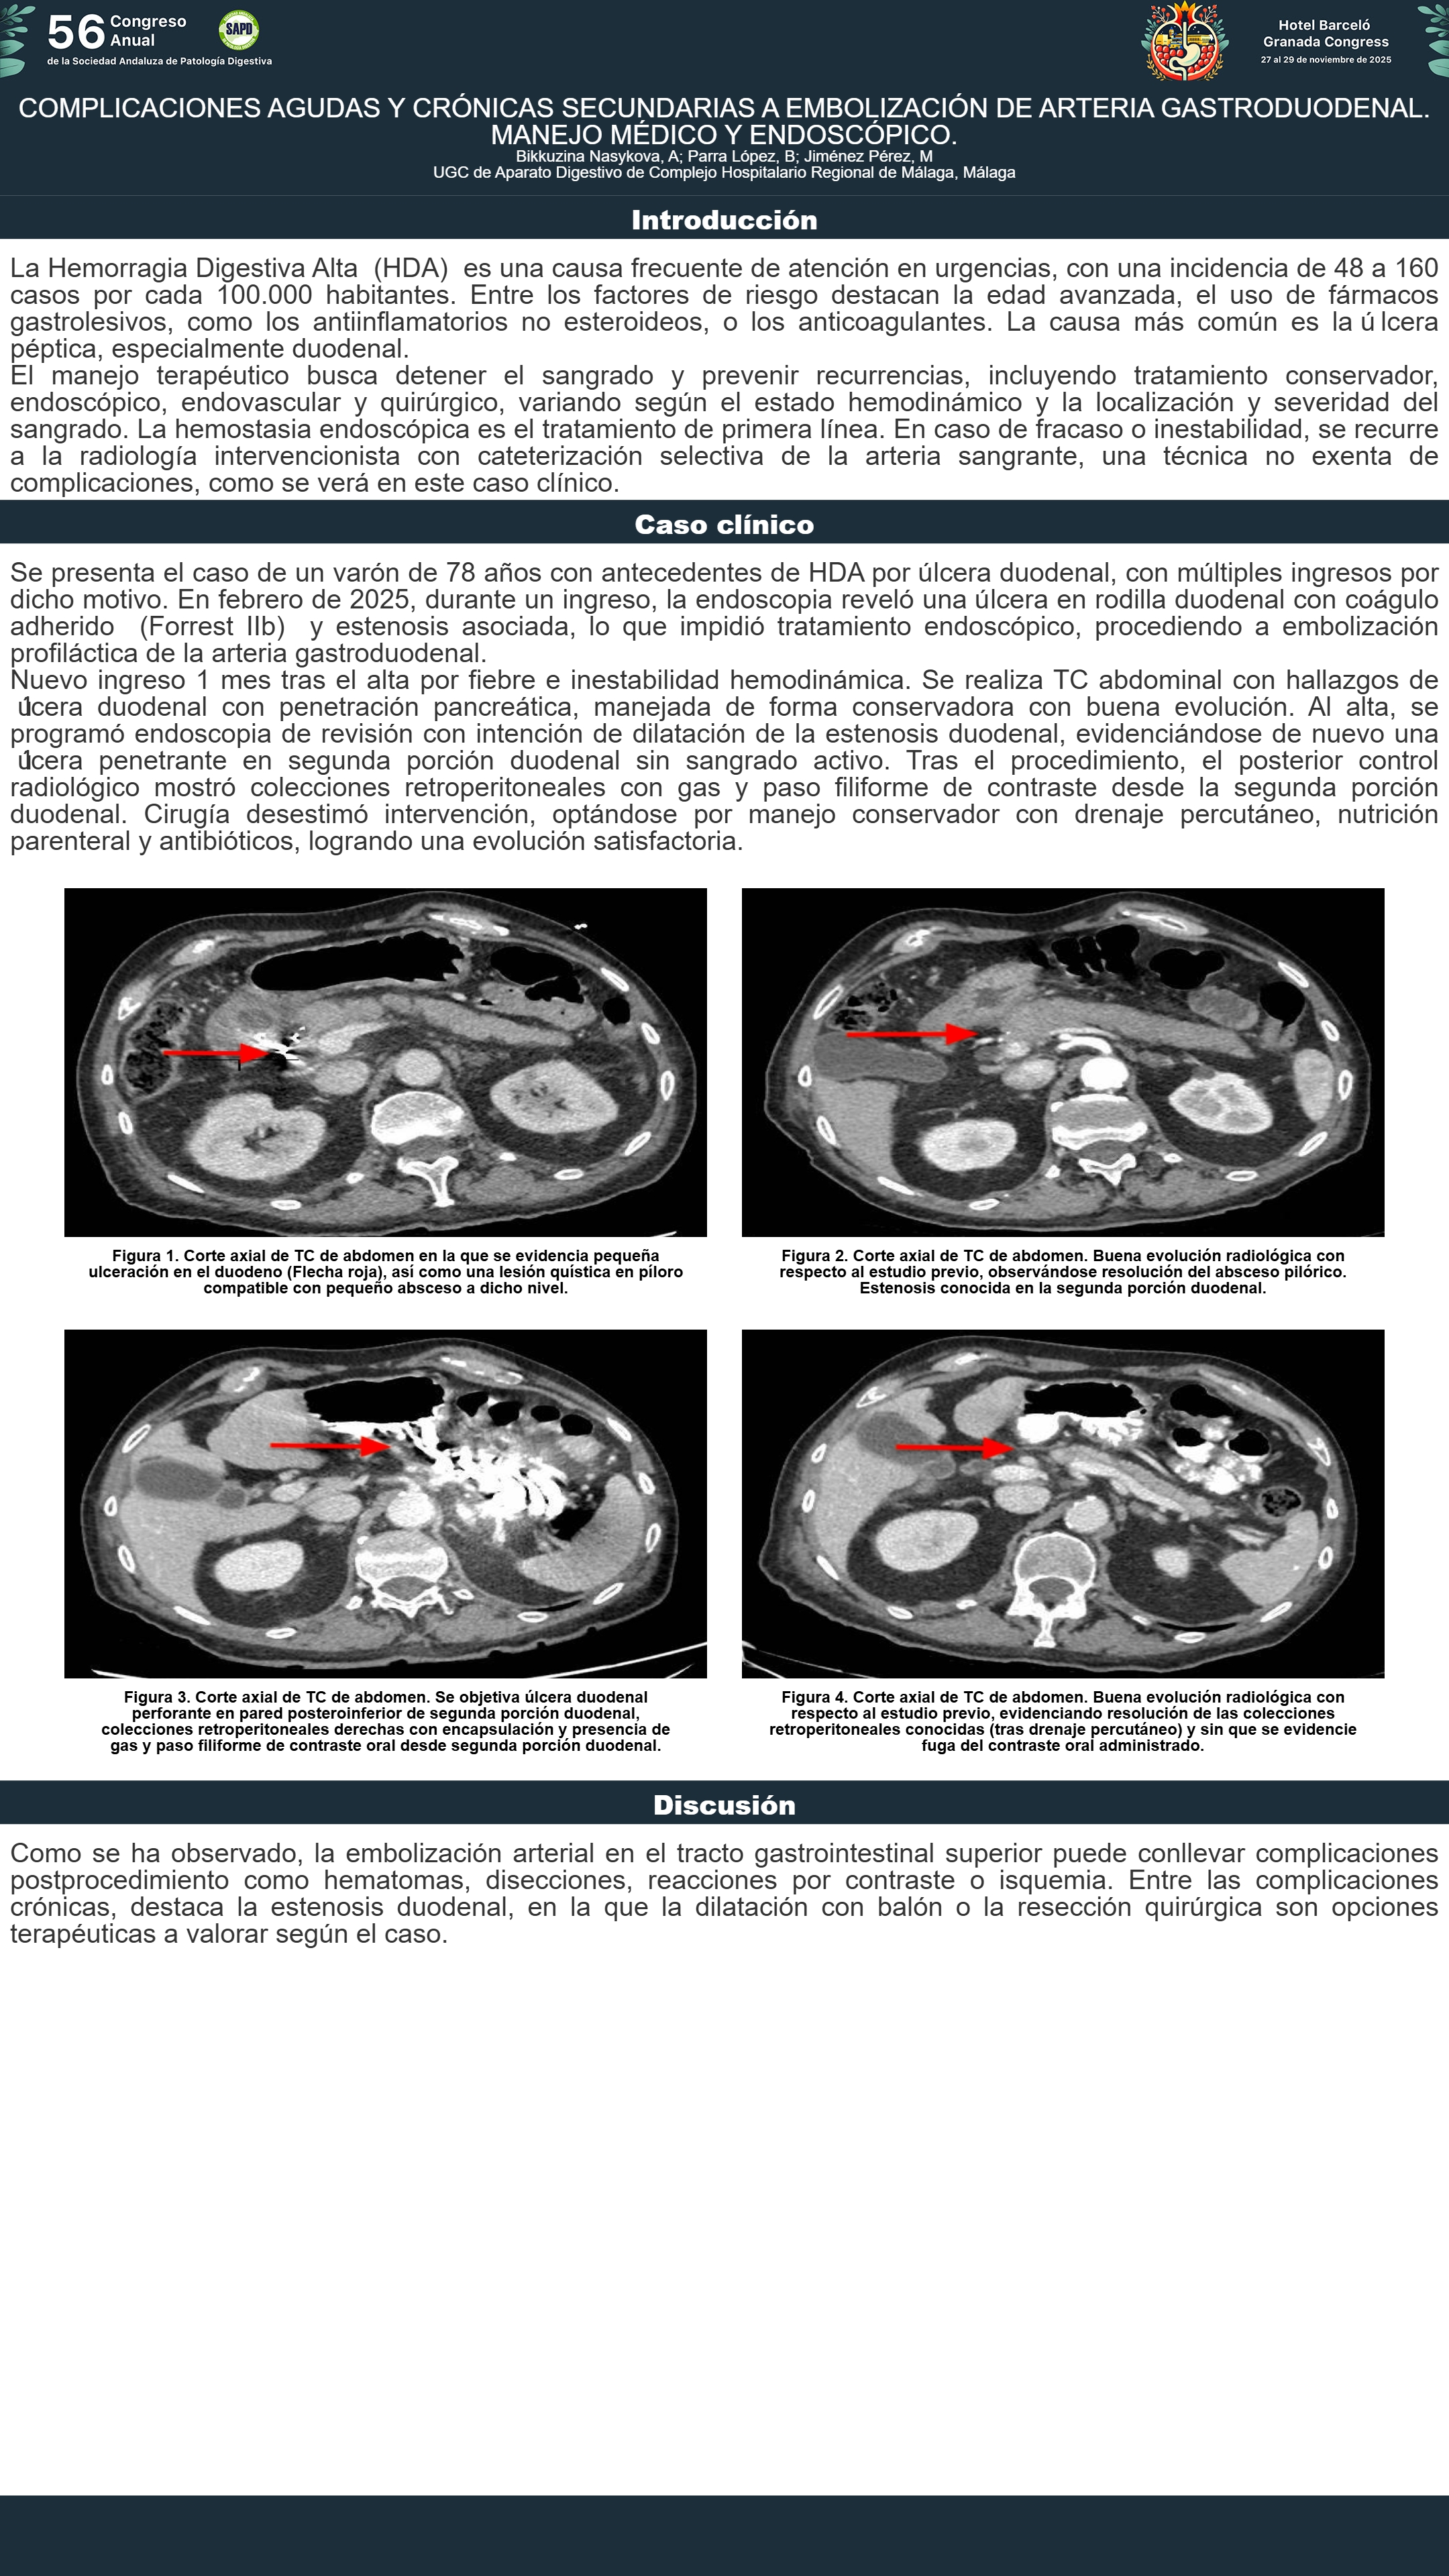

[CP-182] COMPLICACIONES AGUDAS Y CRÓNICAS SECUNDARIAS A EMBOLIZACIÓN DE ARTERIA GASTRODUODENAL. MANEJO MÉDICO Y ENDOSCÓPICO.